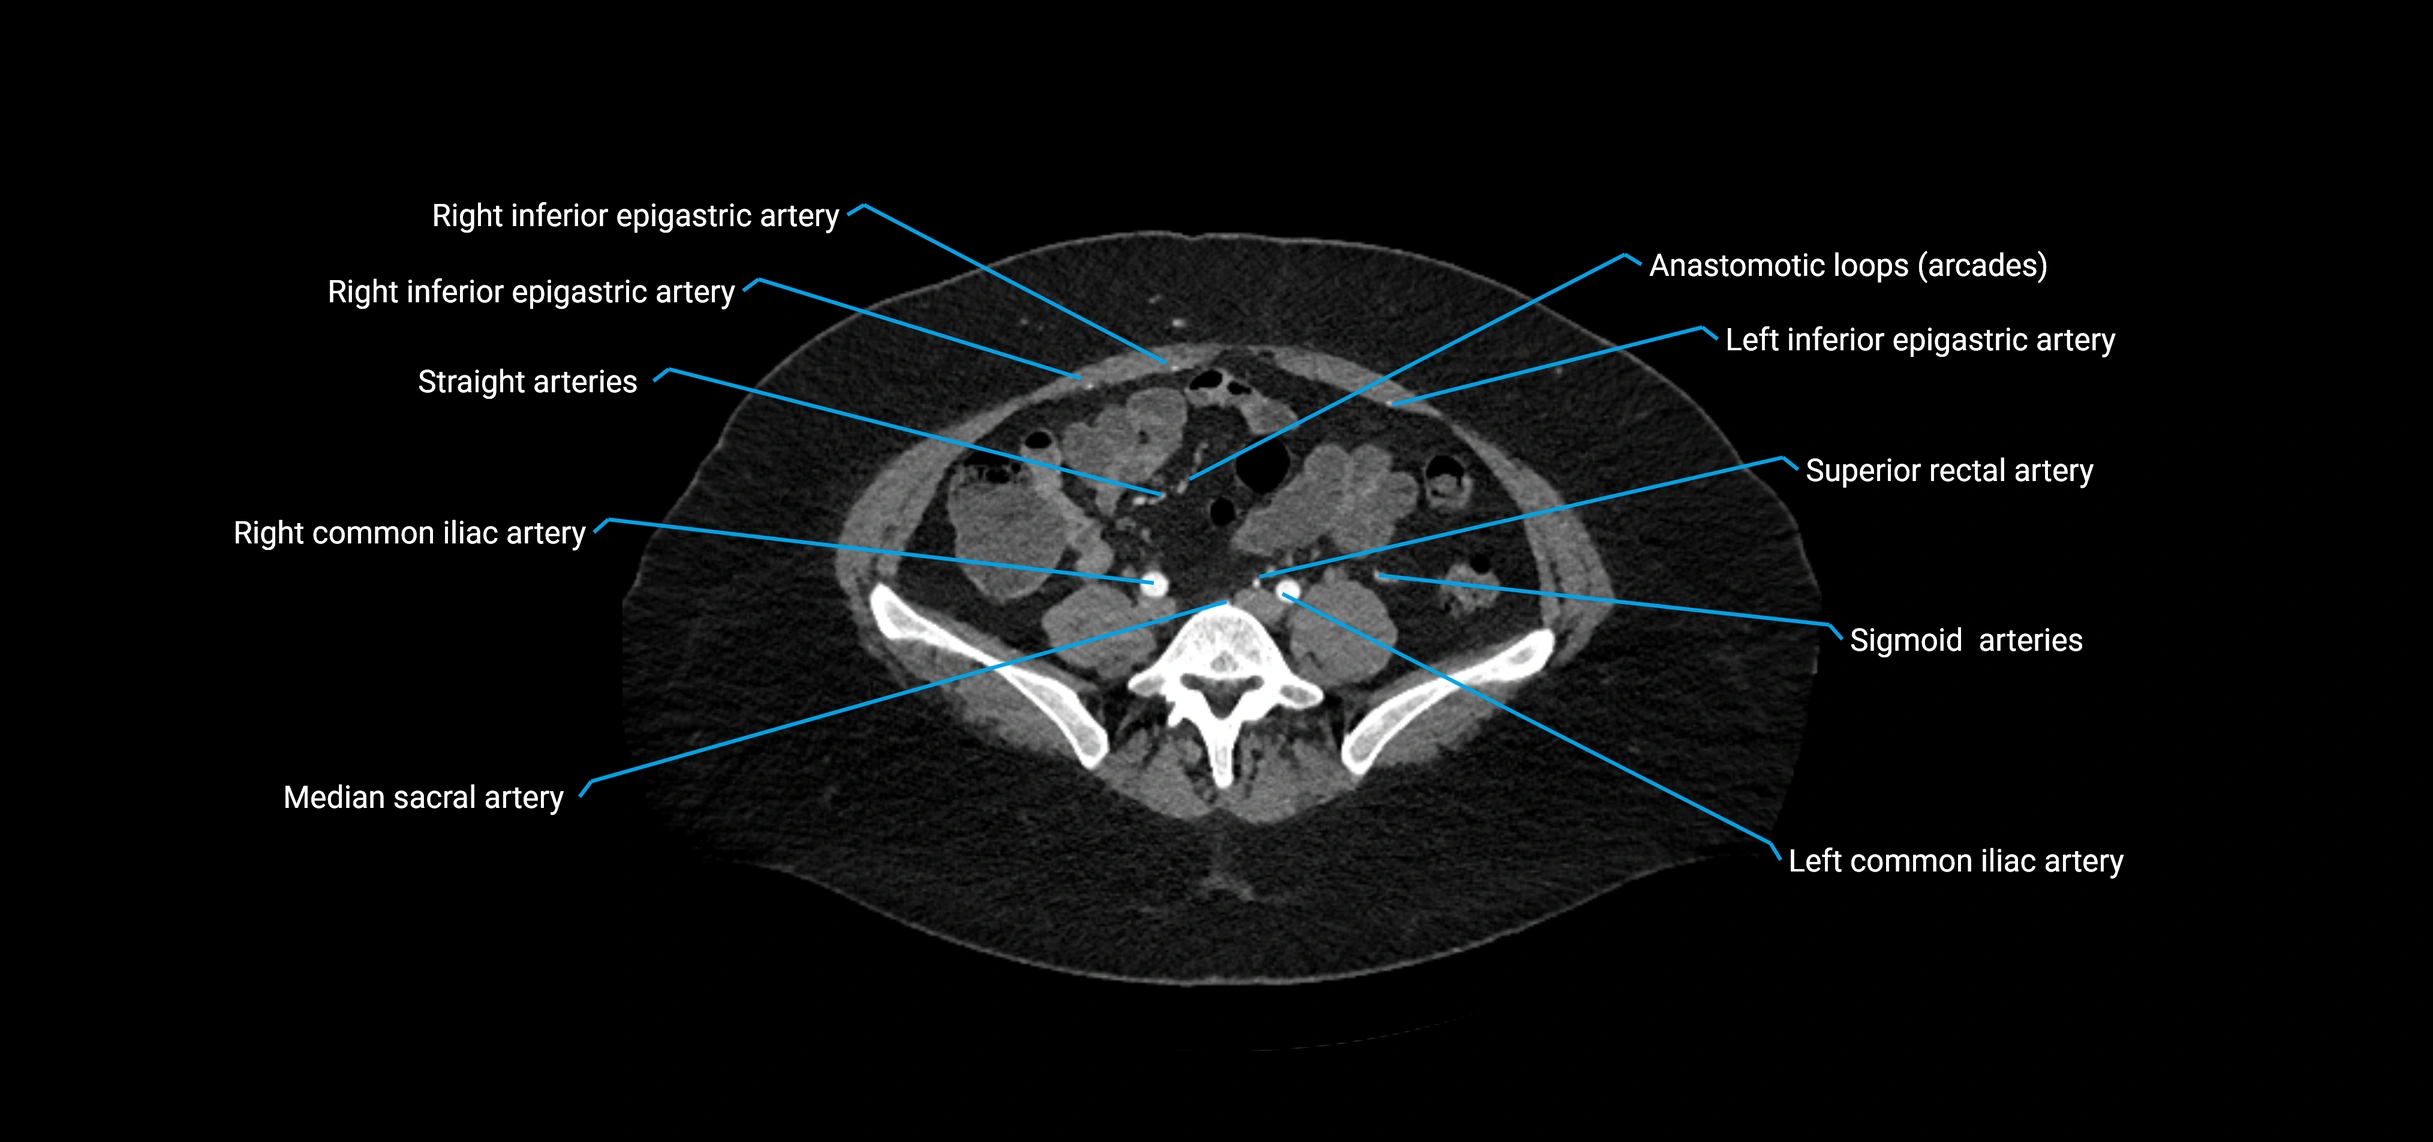

Contrast-enhanced CT (CTA):

• Gold standard for abdominal aortic imaging

• Provides excellent detail of lumen, wall, aneurysm, thrombus, and branch vessels

• Multiplanar and 3D reconstructions help in aneurysm measurement, stent graft planning, and dissection evaluation

• Detects acute rupture, traumatic injury, or occlusion with high sensitivity